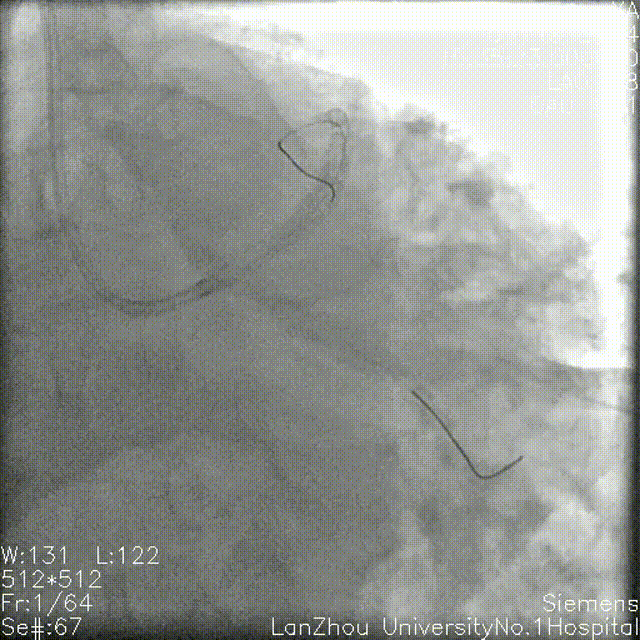

2.75*28mm支架 8atm于前降支近中段释放,复查造影狭窄解除。

复查造影提示回旋支开口仍明显狭窄,考虑使用药球后可能回弹,遂决定行支架植入,于回旋支近端-左主干行Cullotte术,2.75*18mm 10atm释放支架。

前降支Re-wire,1.5mm、2.0 mm、2.5mm球囊扩张回旋支-左主干支架网眼。

与前降支近中段原支架串联前降支近端至左主干 12atm释放3.5*32mm支架。

回旋支Re-wire, 1.5mm、2.0 mm、2.5mm球囊扩张前降支-左主干支架网眼;

2.75*15mm,3.5*12mm球囊扩张前降支-左主干,2.75mm球囊扩张回旋支;

2.75mm,3.5mm 8atm対吻扩张。

复查造影后再次复查前降支IVUS

前降支近中段支架膨胀不全;

遂3.5mm球囊高压扩张;

结合术后IVUS,考虑该处钙化严重及钙化小结导致IVUS导管及球囊无法通过。

复查造影支架贴壁良好